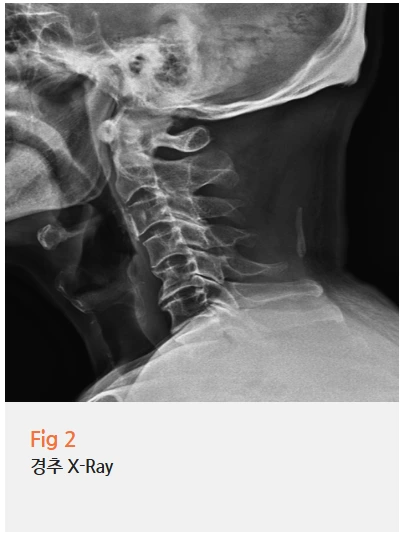

경추 엑스레이를 찍어봤는데, 소견이 꽤 뚜렷하게 나왔어요.

정상적인 목뼈는 옆에서 보면 완만한 C자 곡선을 그리는데,

이분의 목은 그 곡선이 사라지고 거의 일자로 펴진 상태였어요.

여기에 퇴행성 변화도 동반되어 있었고요.

목뼈의 정렬이 무너지거나 디스크 문제가 생기면,

그 주변을 지나는 신경이 자극을 받게 되는데요.

그 신경은 단순히 목에서 끝나는 게 아니라 후두부, 이마, 귀, 눈 주변까지 분포해요.

그래서 목에서 시작된 문제가 머리 전체가 지끈지끈하거나 뒷머리가 묵직하게 아픈 증상으로 이어지는 거예요.

이걸 경추성 두통이라고 해요.